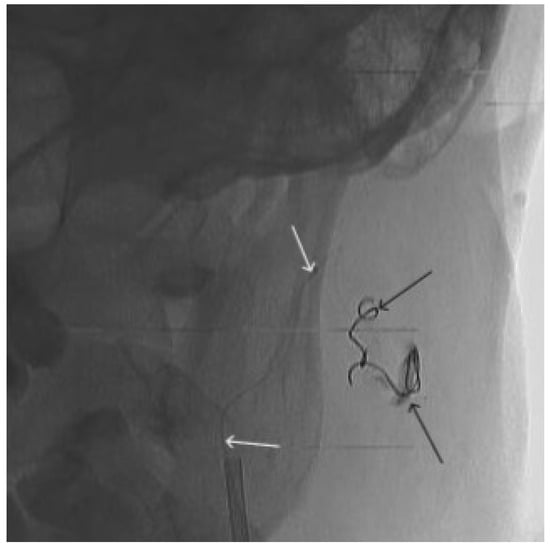

A 48-year-old male patient was admitted to the clinic with complaints of a subcutaneous volume formation in the lower jaw area on the left. Earlier, in another clinic, an attempt was made to embolize the AVM using microcoils. Angiography was performed; filling of the AVM of the soft tissues of the face in the area of the angle of the lower jaw on the left was noted. The presence of separable coils in the afferent from the previous operation was noted; however, the AVM was filled through the coils (Figure 8 and Figure 9). Total embolization of the AVM of the face soft tissues with 7.5 mL of non-adhesive composition ONYX18 was performed. Arteriovenous malformation was totally shut down (Figure 10). There were no complications. The mRs score at discharge was 0.

Figure 9. X-ray, direct projection (the white arrow indicates a microcatheter in the left external carotid artery, the black arrows indicate a complex of microcoils from the previous stage of embolization).